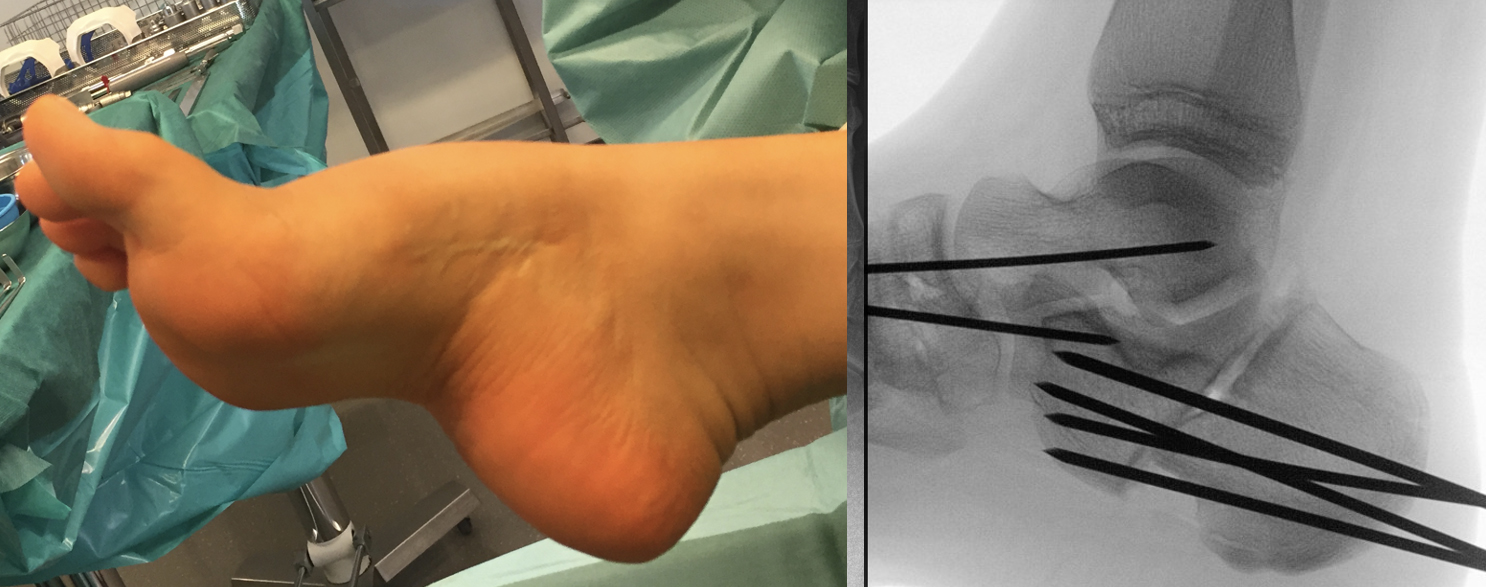

Zusätzlich schränken Wachstumsfugen die Wahl der Osteosynthese ein. Eine die Fuge kreuzende Osteosynthese ist ausschließlich mit Kirschner-Drähten möglich (Abb. 3).

Abb. 3 a-j: Beispiel einer Calcaneusverschiebeosteotomie mit offenen Wachstumsfugen und der entsprechenden Osteosynthese mit Kirschner Drähten. Lokalisation der Osteotomie (a), Lage der Fräse (b-d), Drahtlage mehrere Ansichten (e-h), Heilung der Osteotomie 4 Wochen postoperativ und Entfernung der Drähte (i-j).

Calcaneus-Osteotomie

Die minimalinvasive Calcaneusverschiebeosteotomie bietet eindeutige Vorteile gegenüber dem offenen Verfahren, sodass wir bei Kindern und Jugendlichen nahezu keine offene Verschiebeosteotomie mehr durchführen. Am Calcaneus liegt die offene Wachstumsfuge dorsal. Bei der Durchführung müssen Schenkel der V-förmigen Osteotomie daher etwas steiler angelegt werden, in einem stumpfen Winkel (siehe Abb. 3 a-j). Für die Osteotomie liegen unsere Patienten auf dem Rücken und der BV wird für die exakte Seitaufnahme eingestellt. Der Fuß lagert auf einem hohen OP-Kissen und die Osteotomie kann bequem mit einem langen Kirschner-Draht und einem sterilen Stift angezeichnet werden (Abb. 15).